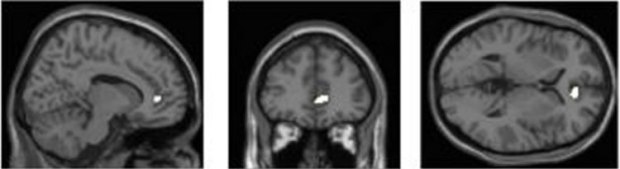

The study by Kep Kee Loh and Dr Ryota Kanai found that grey-matter density in the highlighted region of the brain (anterior cingulate cortex) was negatively associated with the amount of media multitasking activity. Credit Kep Kee Loh & Ryota Kanai.